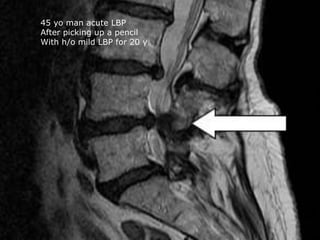

45 yo man acute LBP

After picking up a pencil

With h/o mild LBP for 20 y